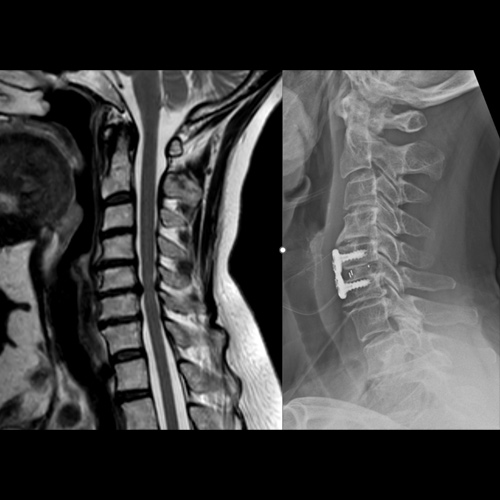

Spinal stenosis (Lumbar) Spinal stenosis (Cervical) Spinal stenosis (Thoracic) Lumbar Disc Herniation Spondylolisthesis Cervical Foraminal Stenosis Vertebroplasty Lumbar Fusion Anterior Cervical Fusion (ACDF) Posterior Cervical Fusion Thoracic Fusion Revision Lumbar Fusion Surgery Facet Joint Cyst Spinal Tumour Minimally Invasive Lumbar Fusion (XLIF) Minimally Invasive Lumbar Fusion (ALIF) Lumbar Fusion (TLIF) Thoraco-lumbar Fusion Lumbar Corpectomy Complex Lumbar Spine Surgery (Spino-pelvic fixation) Complex Cervical Spine Surgery Complex Thoracic Spine Surgery Occipito-cervical Fusion Minimally invasive surgery for thoracic disc herniation Other Related Topics